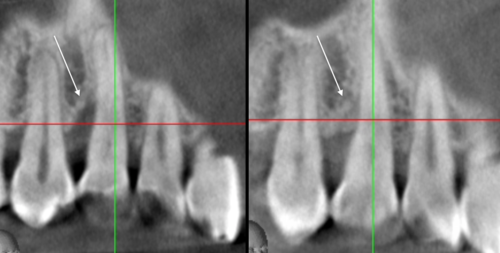

レントゲン的にも骨がないことが確認できます

しかし、ここに再生療法を行うと・・・

黒いところが、白くなっている、つまり骨が出来た、再生したということです